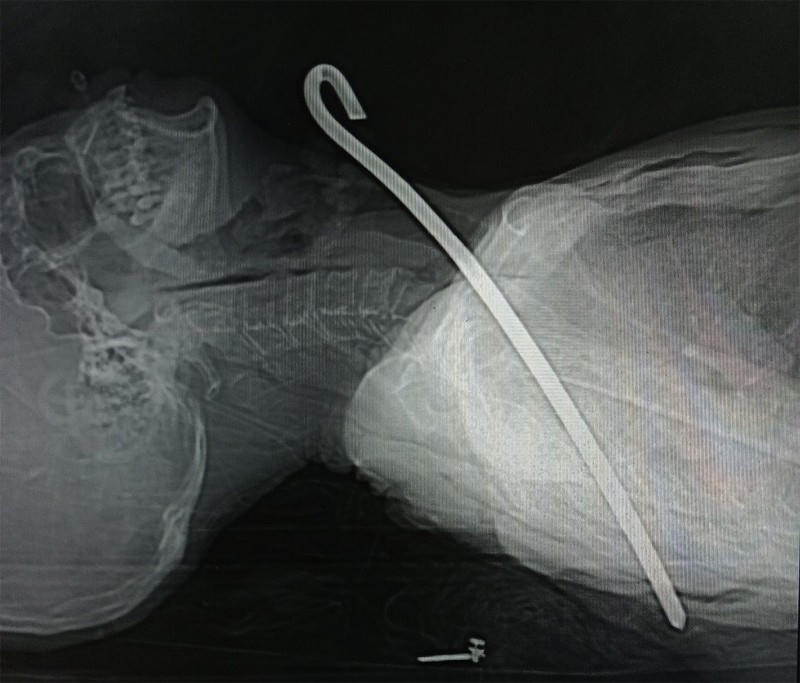

Ngày 9/3, thông tin từ Bệnh viện Đa khoa tỉnh Hà Tĩnh, đơn vị vừa cứu sống thành công một bệnh nhân bị dị vật kim loại dài 30 cm đâm xuyên từ vùng cổ qua phổi.

Trước đó, tối ngày 26/2, Bệnh viện Đa khoa tỉnh Hà Tĩnh tiếp nhận bệnh nhân V.C.Đ. (67 tuổi, trú tại xã Kỳ Tiến, huyện Kỳ Anh, tỉnh Hà Tĩnh) trong tình trạng trụy mạch, suy hô hấp… do bị một dị vật kim loại đâm thấu cổ.

Thanh sắt dài đâm thâu cổ ông Đ.

Ông Đ. bị tổn thương rách thùy trên phổi phải, tràn khí màng phổi trái, tràn khí dưới da thành ngực và vùng cổ, gãy cung sau xương sườn số 5, 6 bên trái, gãy xương bả vai trái…

Ông được người nhà đưa vào bệnh viện cấp cứu trong tình trạng bị thanh sắt dài 30cm xuyên từ vùng cổ qua phổi phải và trung thất xuống vùng ngực.